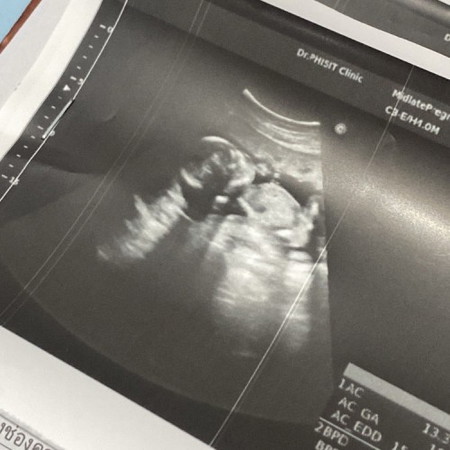

อยากสอบถามความคิดเห็นแม่ๆค่ะ ว่าเจ้าจิ๋วของเราดูศีรษะโตผิดปกติมั้ย ตอนนี้น้อง19w+3d แล้วค่ะ🥺

ปกติค่ะ บอดี้เด็กในท้องจะไม่เหมือนเรานะแม่